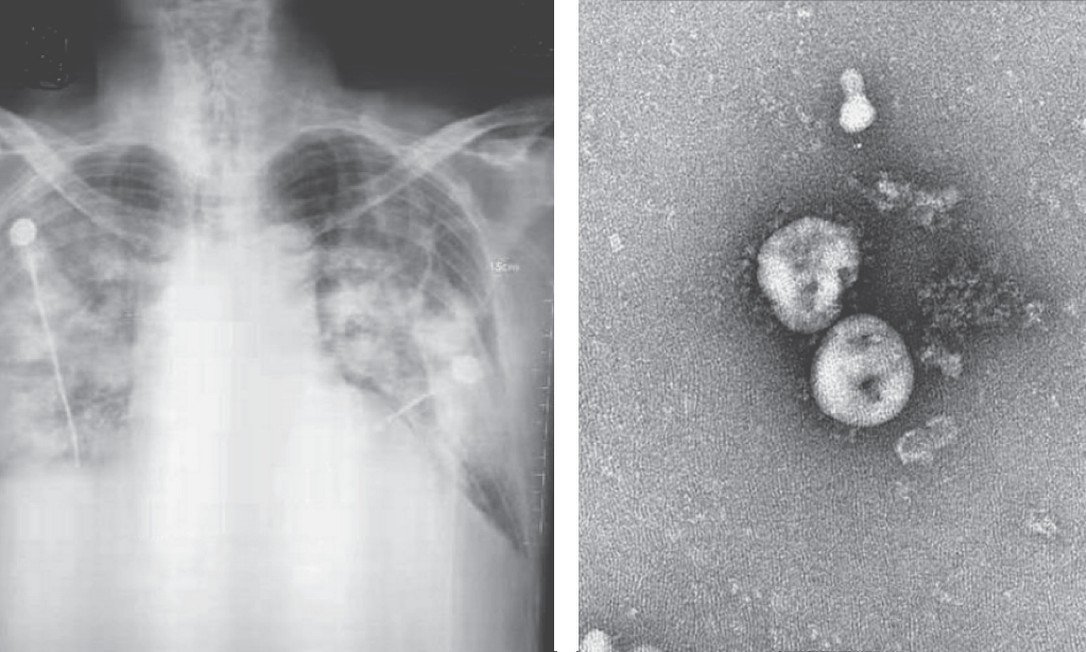

Fernando Benicchio, estudante da USP, apresenta sintomas de coronavírus desde o dia 3 de março. O jovem apresentou crises constantes de tosse e uma febre de mais de 39°C e decidiu procurar ajuda.

Depois de buscar em três lugares diferentes, Fernando conseguiu ser testado no dia 10 de março. Mas o resultado ainda não saiu.

O estudante recebeu um atestado de afastamento por 14 dias, com a numeração CID indicando uma infecção respiratória por coronavírus. Desde então, ele recebe ligações diárias da vigilância epidemiológica checando seu estado de saúde e o de sua mãe.

Porém, passados sete dias desde o exame, ele ainda não sabe se de fato teve a covid-19 ou não. Por segurança, decidiu fazer o autoisolamento.